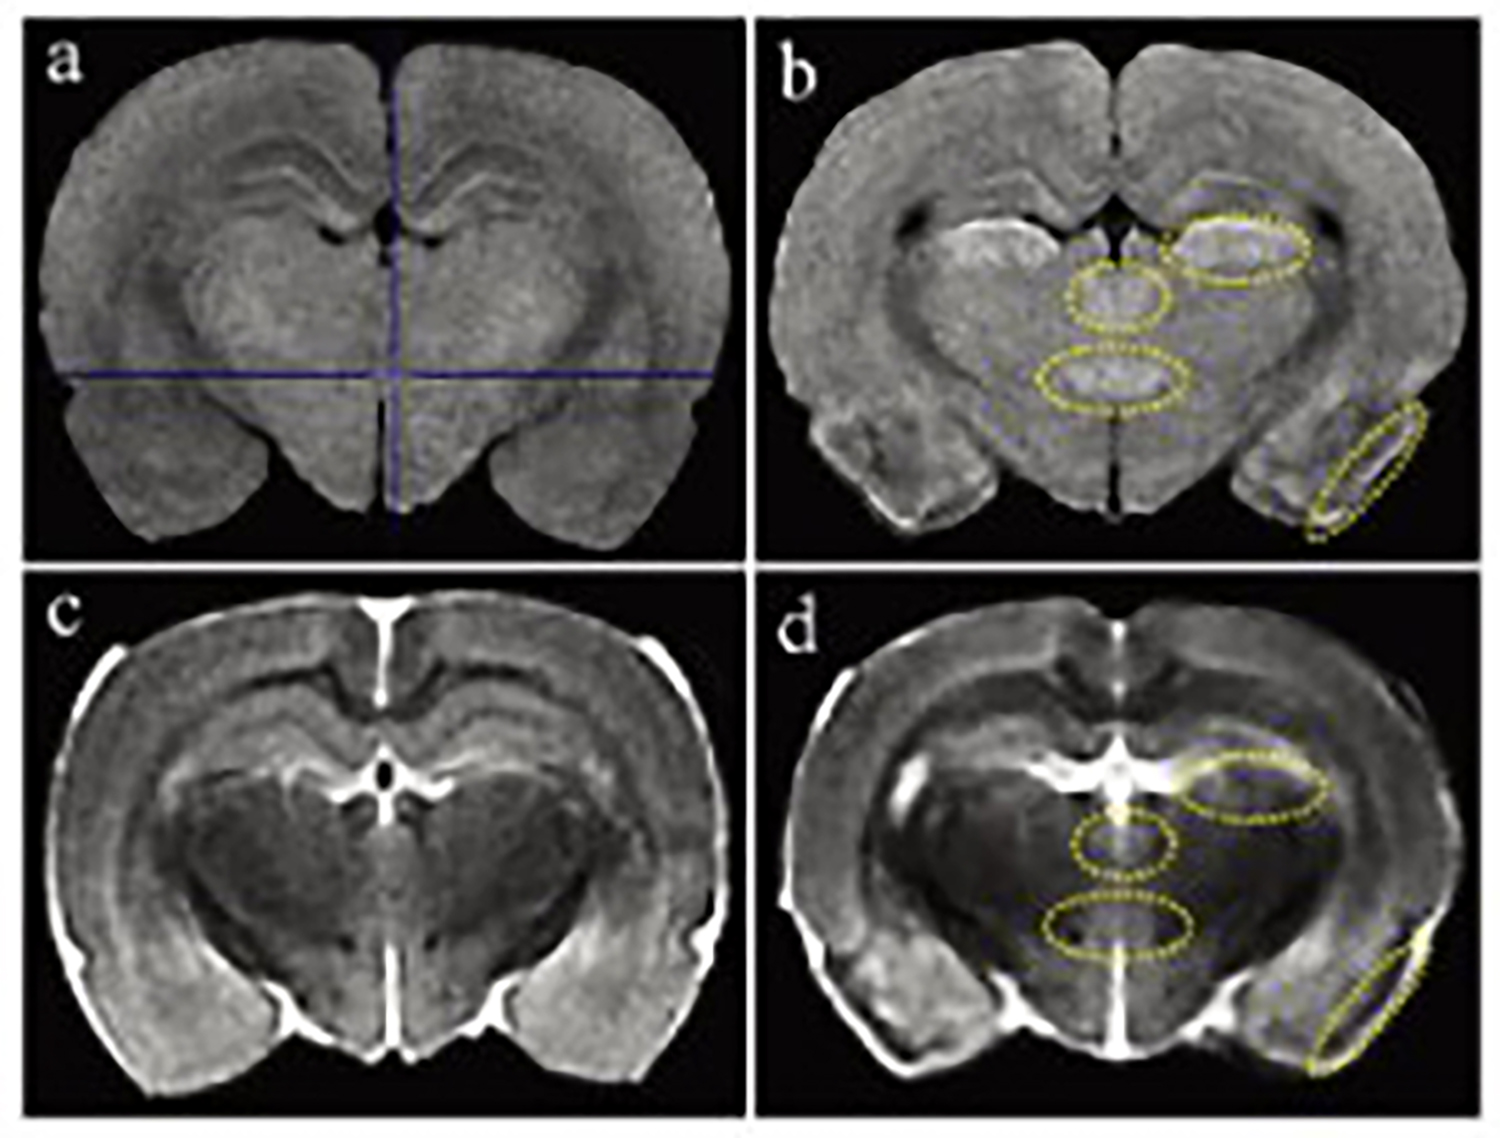

磁共振成像(MRI)广泛应用于临床前研究和药物开发,是一种强有力的无创性方法,可用于评估小鼠疾病模型的表型和治疗效果。

小动物磁共振成像(MRI)是一种强大的非侵入性工具,可用于检测临多种病变。